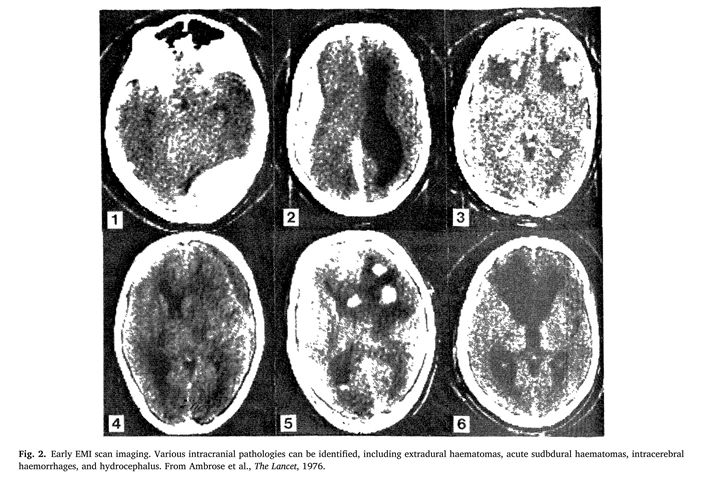

这一时期有几个关键因素促进了GCS在全球范围内的成功。1974年,格拉斯哥是英国仅有的五个拥有 EMI 扫描仪(由 Electric and Musical Industries生产,就是现在广为人知的计算机断层扫描仪,即CT)的中心之一。该设备由EMI的Godfrey Hounsfield爵士设计,于 1971年首次用于临床,五年内全球有超过1000台EMI扫描仪投入使用。普遍流传披头士乐队唱片销售收入资助了其研发,但实际上英国卫生与社会保障部的财政资助更为重要。考虑到之后计算力的大幅提升,按照今天的标准,早期EMI扫描仪提供的图像显然是原始的,但这些早期的脑扫描至少能识别与意识改变相关的颅内病灶,并指导治疗,包括手术(图2)。将患者的GCS与术前放射学诊断相结合,对治疗和预后判断都具有重要价值。